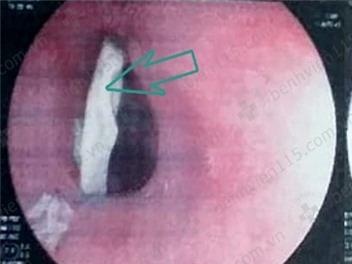

Các bác sĩ đã chỉ định nội soi dạ dày, kết quả phát hiện dị vật cắm sâu vào thực quản, gây hai ổ áp-xe chảy nhiều dịch mủ, cách cung răng trên khoảng 20 cm. Bệnh nhân T. được tiến hành gắp dị vật, làm sạch ổ mủ, cầm máu. Dị vật là mảnh xương gà có hai đầu sắc nhọn dài khoảng 4 cm.